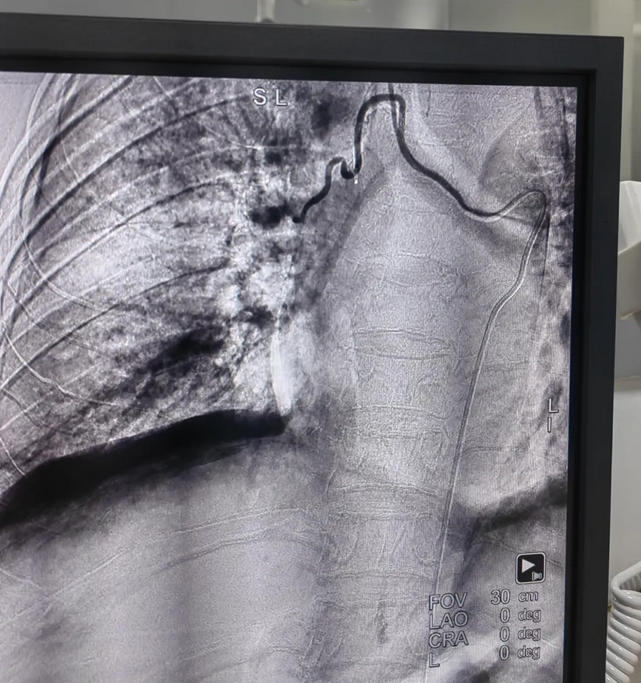

栓塞前支气管动脉楼

支气管动脉栓塞后

经过详细讨论和评估,专家们一致认为,患者的情况适合进行肺支气管动脉造影术+栓塞术。随即,外三科为患者制定了手术方案。手术过程中,在遵义医科大学第二附属医院帮扶专家梁乐乐、韦旭的指导下,外三科医生团队凭借精湛的技术和丰富的经验,在X光透视的引导下,精准找到出血的血管,并成功注入了栓塞剂,堵塞了出血点。整个手术过程十分顺利,患者未出现任何并发症。

据了解,肺支气管动脉栓塞术是一种微创的介入治疗手段,主要针对各种原因引起的咯血,特别是对于内科药物治疗无效、反复咯血的患者,具有显著的治疗效果。该手术通过在患者的股动脉插入导管,利用X光透视技术将导管精准送至病变的肺支气管动脉,然后注入栓塞剂,迅速堵塞出血的血管,从而达到止血的目的。